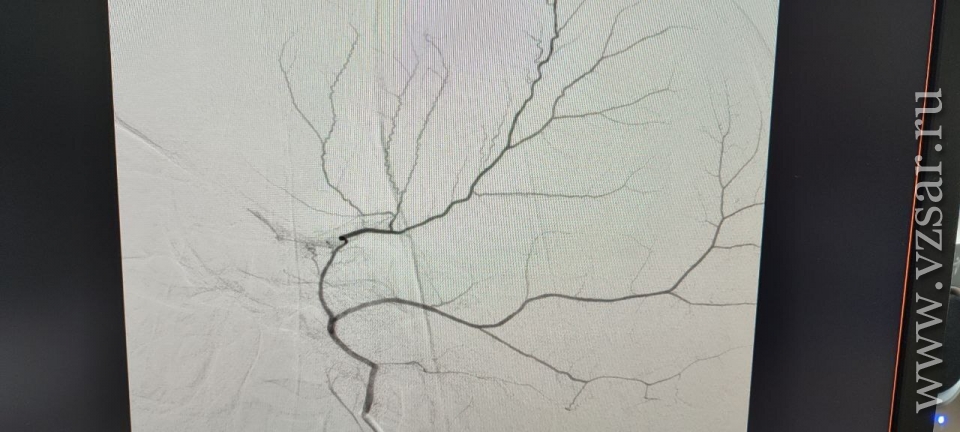

Суть новой эндоваскулярной методики заключается в прицельной внутрисосудистой закупорке этой артерии, что прекращает питание капсулы гематомы и способствует ее постепенному рассасыванию, не влияя на кровоснабжение головного мозга.

Медики успешно выполнила эндоваскулярную эмболизацию средней оболочечной артерии слева микрочастицами. Уже через 4 суток исследование показало значительное уменьшение гематомы - на 20%, а смещение мозга уменьшилось вдвое.